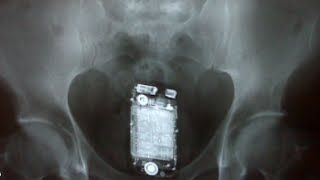

http://youtu.be/PC47l6sMuPU Top 10 Strangest Objects in an X-Ray Yes, that's a Grenade. Some of the weirdest things to end up in the human body. Enjoy! Top 10 Strangest Found in a Human Body Music By: "Bent and Broken" Kevin MacLeod (incompetech.com) "Run Amok" Kevin MacLeod (incompetech.com) Licensed under Creative Commons: By Attribution 3.0